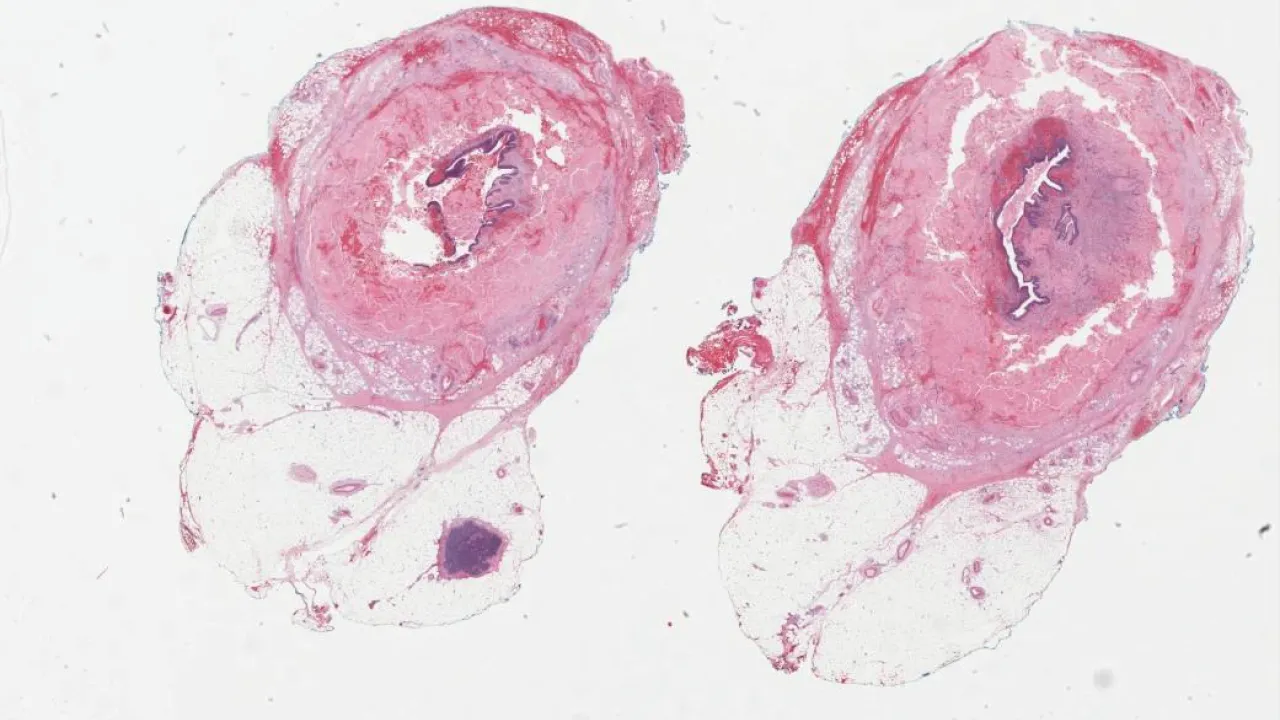

Lower Urinary Tract and Male Genital System

Subscribe to Lower Urinary Tract and Male Genital System